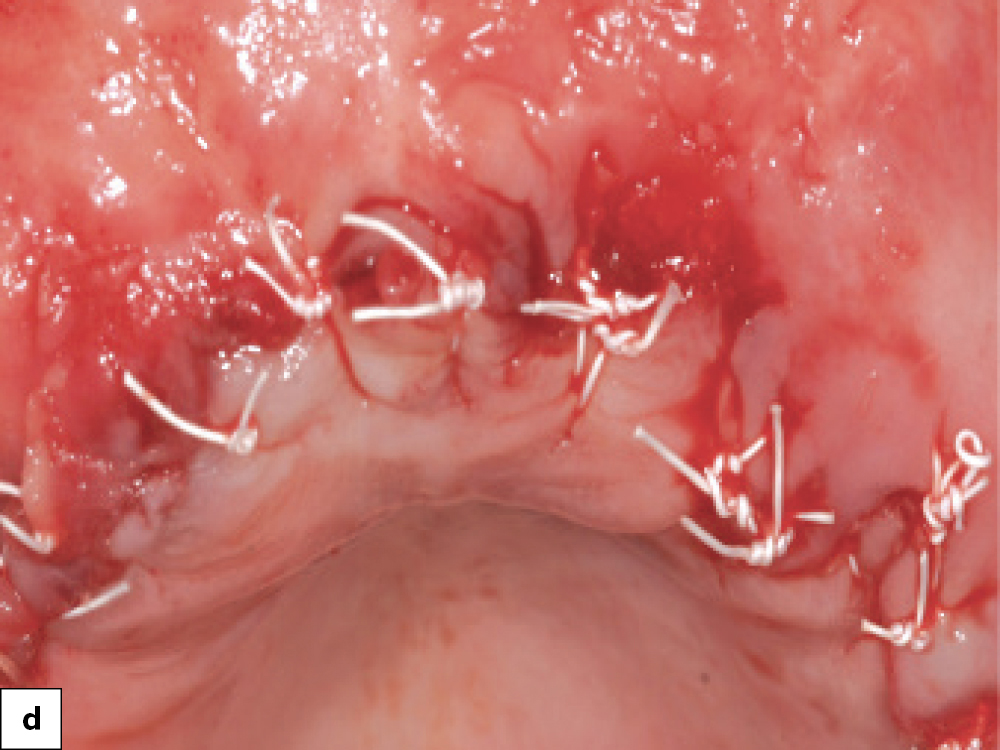

Implant Placement in Bony Defects

Newport Biologics Allograft Placement

Newport Biologics Collagen for Containment

Final Closure

Immediate implant placement and defect grafting: (a) Implant placement in areas where bony defects are present; (b) Newport Biologics Cortico/Cancellous Allograft Blend is placed into the defects and condensed with a bone packer; (c) A Newport Biologics Resorbable Collagen Membrane 4–6 is placed over the grafted area to contain graft material and prevent the migration of soft tissue into the fenestration during healing; (d) Final closure.